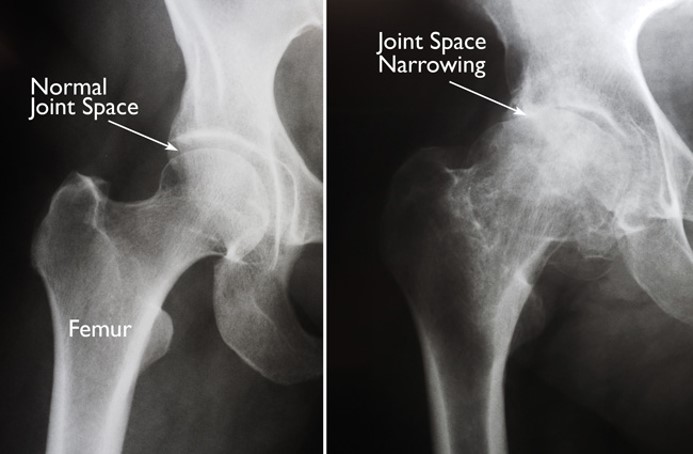

The bones in your skeleton do not rub against each other when they meet at a joint, they have a special cushion in between them so we can bend without pain. The scientific, name for this cushion is cartilage.

- have less cushioning (cartilage) between then.

This means when joints move they can be very painful and become inflamed (swollen).

In the x-ray above, the picture on the left is a normal hip joint, and on the right is an old damaged one.